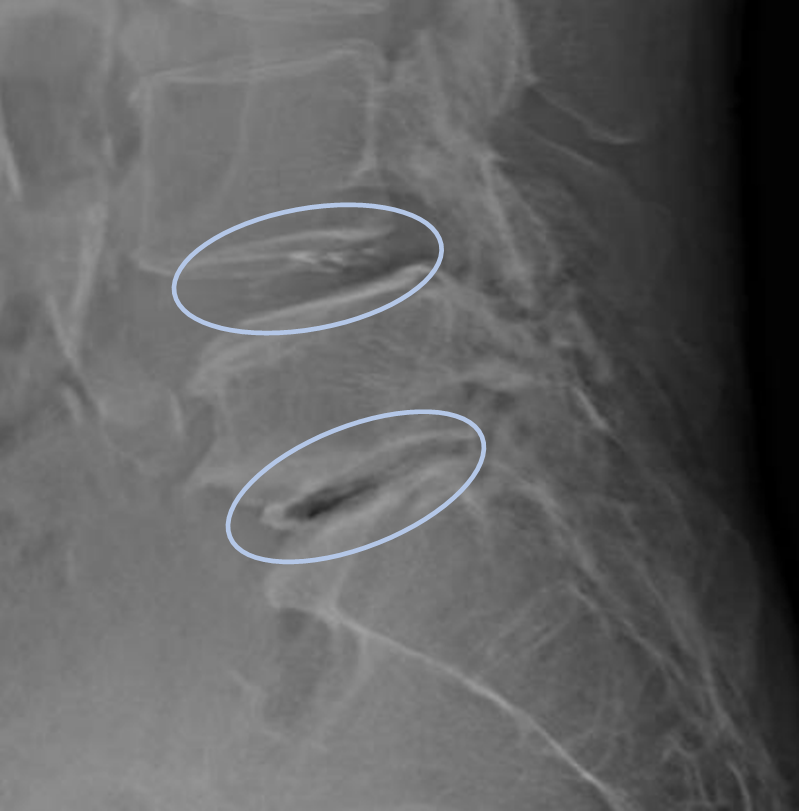

患者様と相談の元、L4/5,5/sにセルゲル法を施行

DiscoGelを入れた後の画像になります。